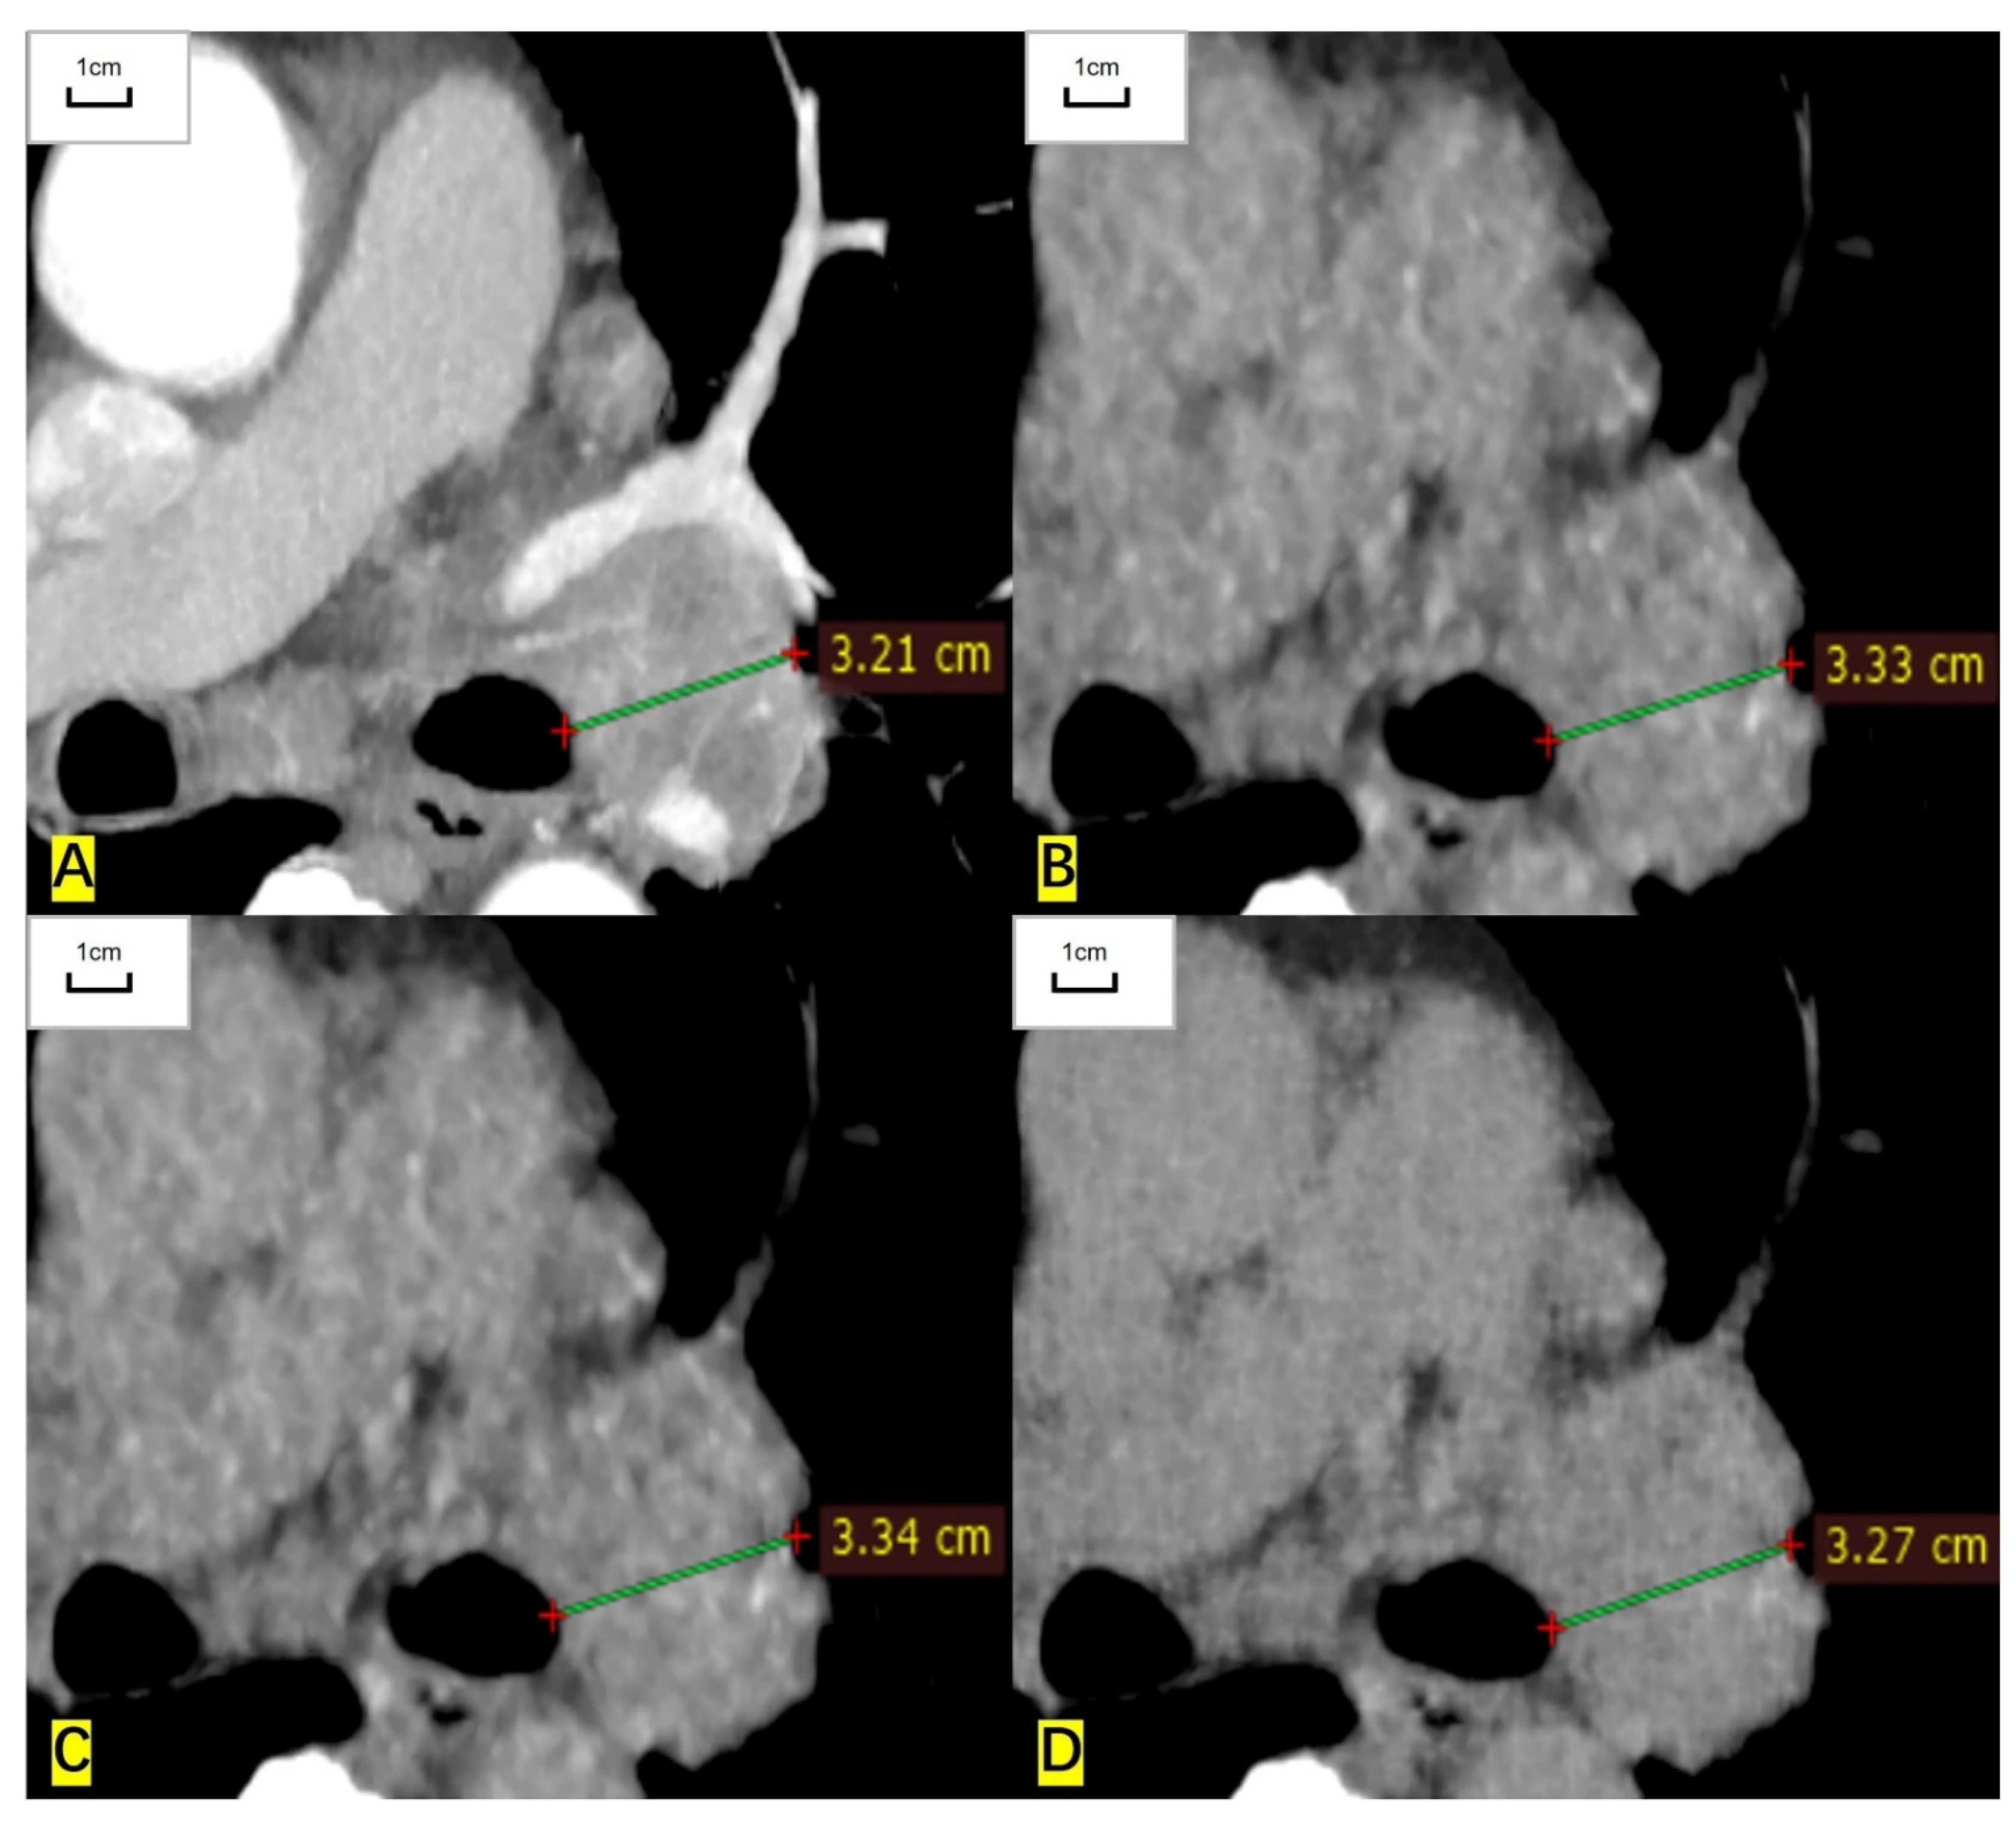

Figure 2.

A 75-year-old woman had a lymph node in the left hilum and the histological result was adenocarcinoma. (A) The short diameter measured on the contrast-enhanced CT image is 32.1 mm. (B) The measured short diameter on the ASIR-V-80% reconstructed image is 33.3 mm. (C) The measured short diameter on the DLIR-M image is 33.4 mm. (D) The measured short diameter on the DLIR-H images is 32.7 mm. The short diameter is overestimated by 3.7%, 4.0%, and 1.9%, respectively, compared with that of contrast-enhanced CT.

For RECIST-defined pulmonary target lesions, the correlation coefficient of measured diameter between ULDCT and contrast-enhanced CT was 0.999 (95% CI: 0.998 to 0.999), 0.998 (0.997 to 0.999), and 0.999 (0.999 to 1.000) for ASIR-V-80%, DLIR-M, and DLIR-H images, respectively. For mediastinal lymph nodes, the correlation coefficient was 0.997 (0.995 to 0.999), 0.997 (0.995 to 0.998), and 0.999 (0.998 to 1.000), respectively. For hilar lymph nodes, the correlation coefficient was 0.993 (0.979 to 0.997), 0.995 (0.984 to 0.998), and 0.997 (0.991 to 0.998), respectively. The measured diameters of target lesions in ULDCT were highly correlated with those in contrast-enhanced CT (Table 2, Figure 1 and Figure 2).